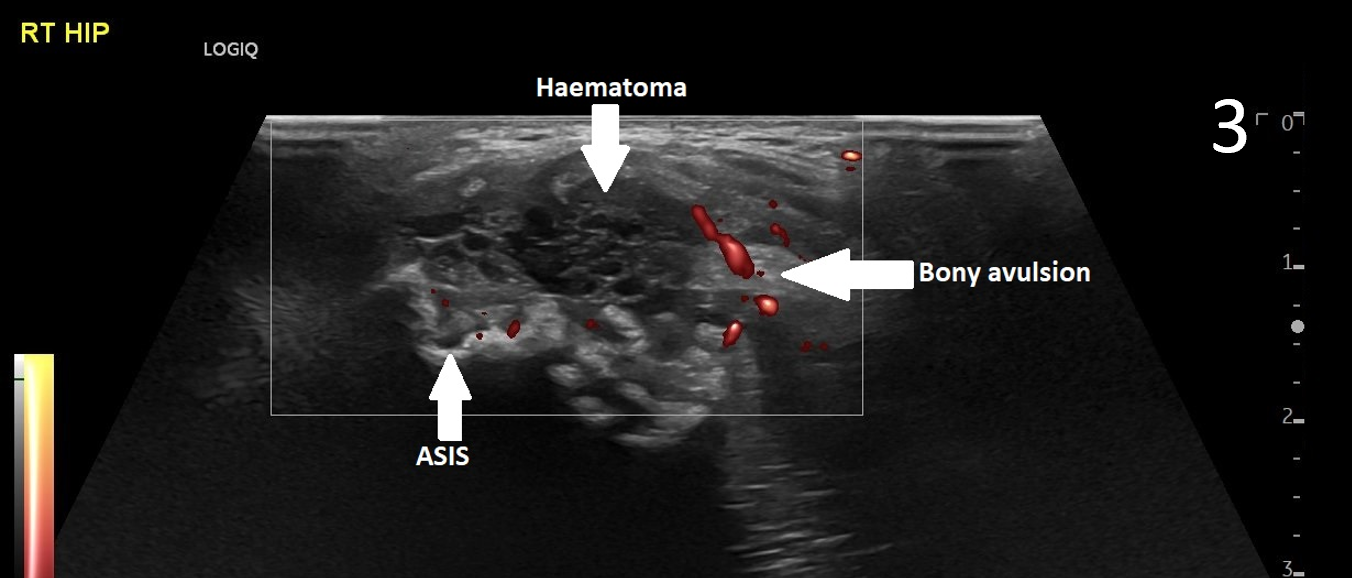

A 17-year-old male presented with severe pain in his right groin. He felt a ‘pop’ in his right groin whilst sprinting and was struggling to weight-bear. A radiograph excluded any bony abnormality (Figure 1) and an ultrasound scan showed no evidence of inguinal or femoral hernia.

The patient was focally tender in the right iliac fossa at the level of the anterior superior iliac spine (ASIS). At this site, there was muscle fibre disruption and a haematoma at the insertion of the sartorius tendon with minimal retraction (Figure 2). There was cortical irregularity at the ASIS and a bony fragment within the retracted tendon and also neovascularisation here on power Doppler (Figure 3). On comparison to the contralateral side, there was altered architecture of the sartorius muscle with a clear defect while the left side looked normal (Image 4). Ultrasound appearances in keeping with a sartorius tendon avulsion. This was treated conservatively with rest, analgesia and a return to normal activities after two months. Surgical interventions are uncommon and are reserved for when the fracture fragment has migrated more than 3cm.

This injury is associated with young athletes plus young rugby and football players.